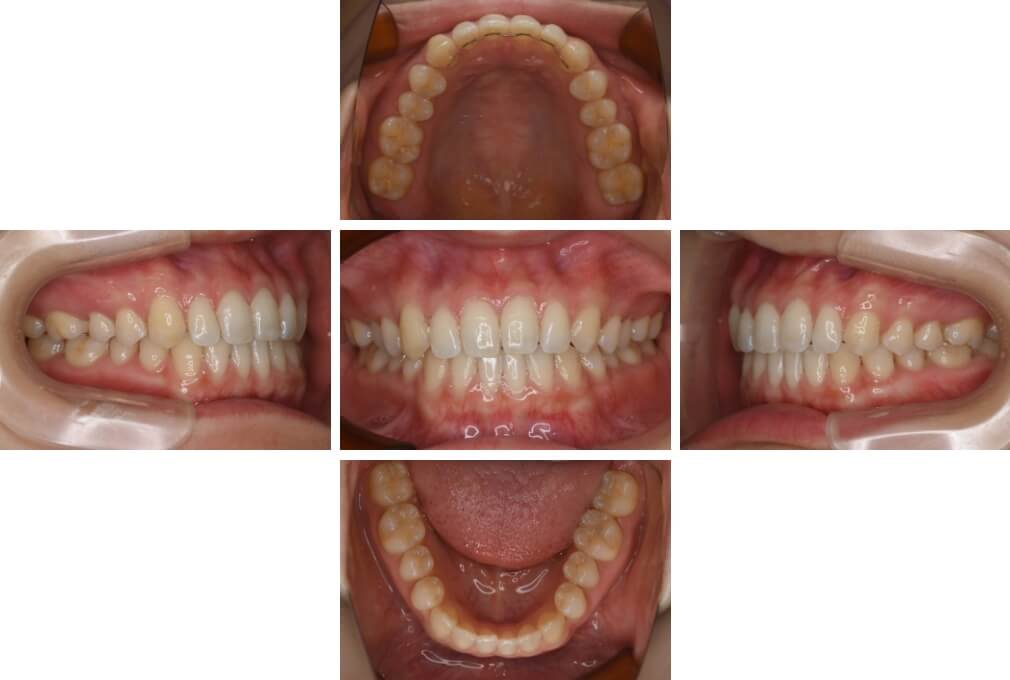

CASE:03

上下顎前突

初診時年齢 18歳4か月

性別 男性

治療費の目安 105万円程度(治療開始時)

歯列の乱れは著しくなく上顎右側側切歯が捻転し口蓋側へ転位していた。また、問診の中で患者さんから最も重視する治療結果として口元の突出の改善の申出があった。下顎が後退した上顎前突傾向ではあったが著しいものではなかった。上下顎前突と診断し上下顎小臼歯抜歯を行っていただき、上下顎舌側マルチブラケット装置を使用して、矯正用アンカースクリューを併用して動的治療を行った。上下顎前歯の後退を十分行い口元の突出感も改善した。治療後10年1か月の来院時には口元の突出感が再発することもなく、下顎前歯の少しの唇舌的なずれはあったが歯列は安定していた。動的治療期間2年2ヵ月間。

治療前

18歳4ヵ月

治療後

動的治療期間2年2カ月間

20歳10か月

10年経過

動的治療終了後10年1カ月

30歳11か月